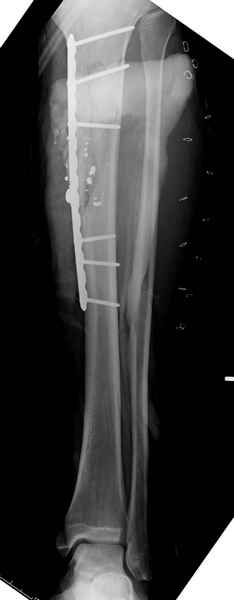

2 перелом бедра

Вложение не в текстовом формате было извлечено…

Имя     : 3 GSW final ap.jpg

Тип     : image/jpeg

Размер  : 25174 байтов

Описание: отсутствует

Url     : http://weborto.net:8080/pipermail/ortho/attachments/20090726/b21ae3ea/attachment-0017.jpg